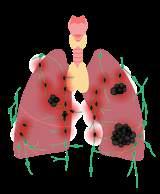

легень: SARS-CoV-2 (а),

стафілокок (б),

приміщеннях. Мал. 17.1. Поширені збудники

дихання. Найбільш поширеними є саме інфекційні захворювання органів дихальної системи. Їх спричинюють віруси та бактерії, які передаються переважно повітряно-крапельним шляхом. Ці збудники разом із краплинками слизу потрапляють у повітря, коли ми видихаємо, та під час чхання чи кашлю. Цей аерозоль, що містить бактерії та віруси, вдихають усі довкола (мал. 17.2). Саме тому хвора людина не має перебувати в місцях скупчення людей, особливо в

Інфекційні захворювання органів

дихання

Інфекційні запальні процеси дихальних шляхів і легень можуть спричинятися різними вірусами (аденовіруси, риновіруси та ін.) чи бактеріями (золотистий стафілокок,